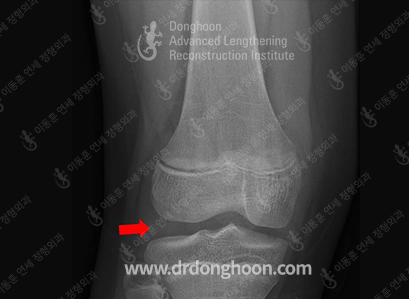

それでは、軟骨と軟骨板はどのように異なるのかから見ていきましょう。 エックス線検査を見れば、骨と骨の間に空間(赤い矢印)がありますが、実はこの空間にはエックス線検査では目に見えない軟部組織ら(soft tissues)があります。